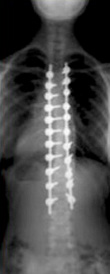

spine x-ray before treatment spine x-ray after treatment